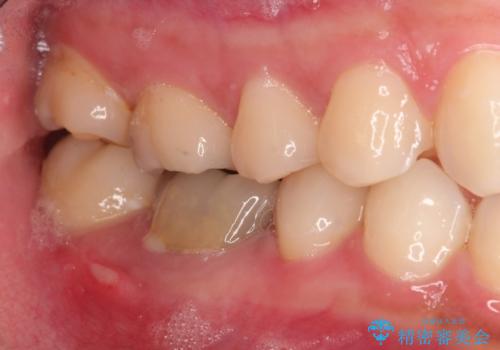

- 右下の奥歯の調子がよくないとのことで来院されました。

レントゲン・口腔内診査をお行い、保存が難しいことがわかりました。

抜歯後インプラントをする計画としました。